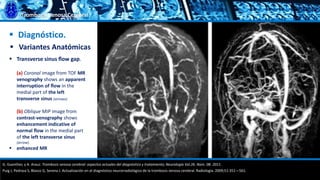

 Diagnóstico.

 Variantes Anatómicas

 Hipoplasia

 Atresia

G. Guenther, y A. Arauz. Trombosis venosa cerebral: aspectos actuales del diagnóstico y tratamiento; Neurología Vol.26. Núm. 08. 2011.

Puig J, Pedraza S, Blasco G, Serena J. Actualización en el diagnóstico neurorradiológico de la trombosis venosa cerebral. Radiología. 2009;51:351—561.

 Oblique MIP image from coronal TOF MR venography shows the complete

absence of the medial part of the left transverse sinus (arrows),

Trombosis Venosa Cerebral

 Transverse sinus flow gap.

(a) Coronal image from TOF MR

venography shows an apparent

interruption of flow in the

medial part of the left

transverse sinus (arrows).

(b) Oblique MIP image from

contrast-venography shows

enhancement indicative of

normal flow in the medial part

of the left transverse sinus

(arrow).

 enhanced MR